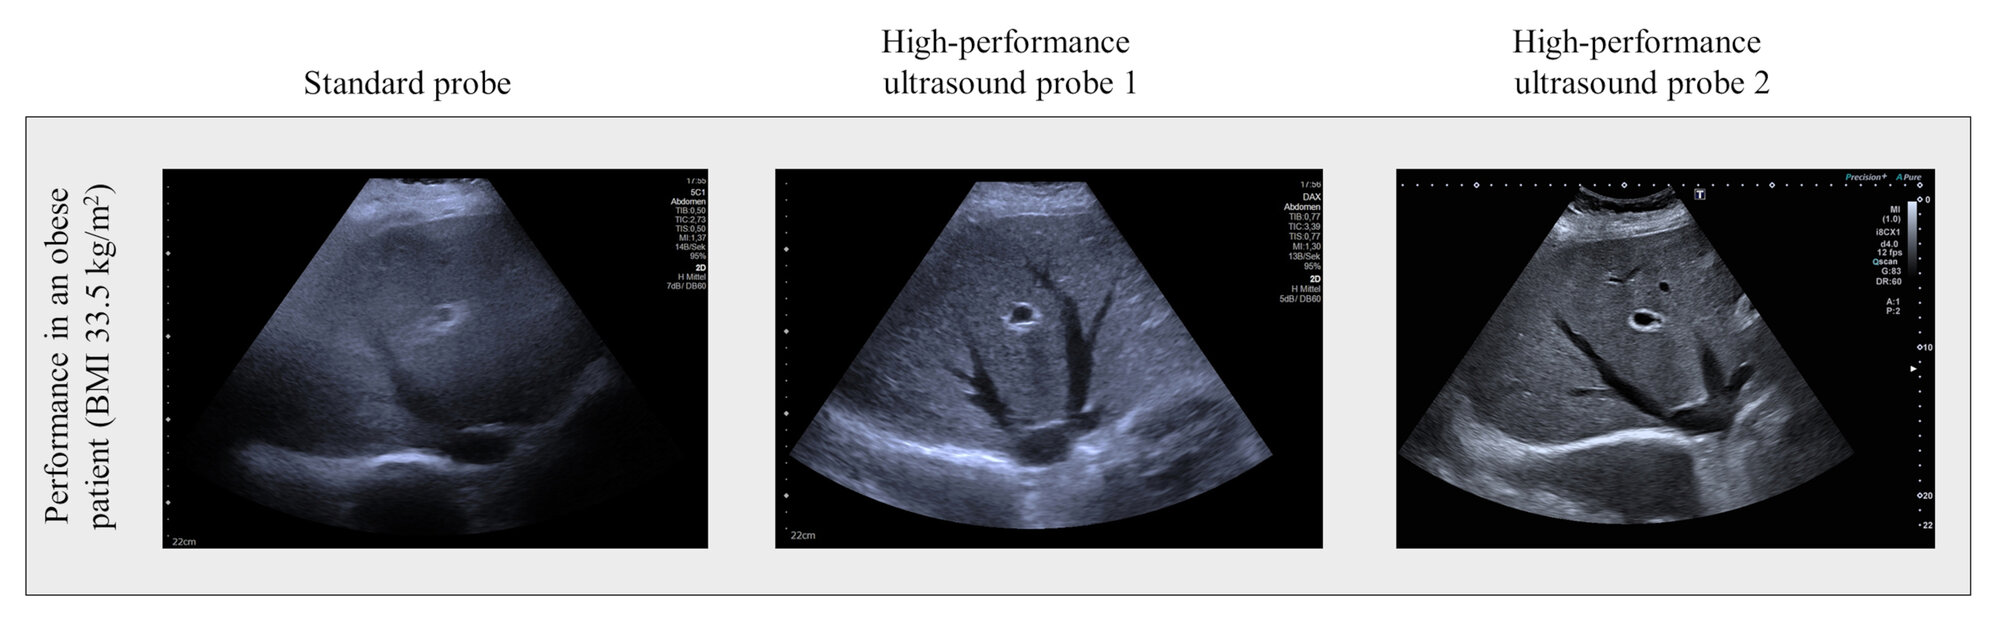

Die aktuellen Daten zeigen, dass die relativ teuren Spezialsonden für Ultraschallgeräte einen relevanten Mehrwert bieten können. Bei den 40 Teilnehmerinnen und Teilnehmern der Studie wurde eine hoch standardisierte Ultraschalluntersuchung des Bauchraums mit drei verschiedenen Sonden, Standardsonde versus zwei Hochleistungssonden, durchgeführt. Untersucht wurden die Leber und die rechte Niere bei Menschen mit verschiedenen Graden des Übergewichts. Die Qualität der Ultraschalluntersuchung wurde anhand eines Punktescores bewertet.